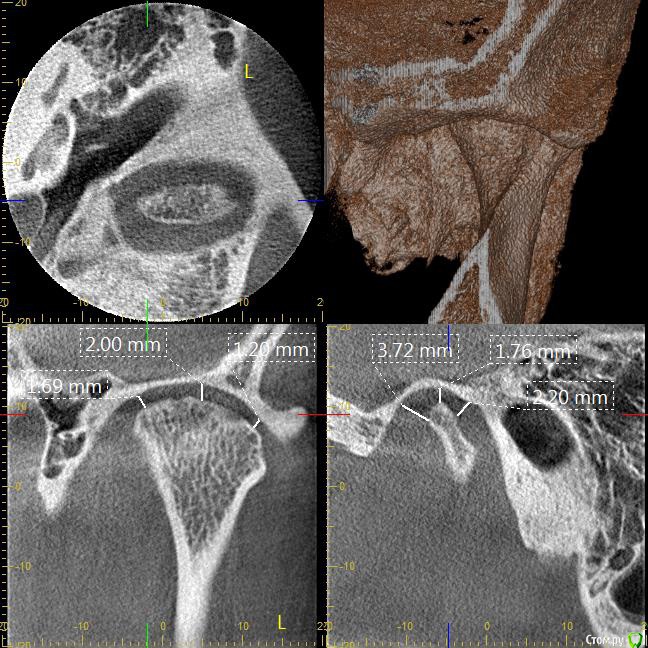

Мне 31 год. В детстве мне выбили верхний зуб 2-ку. Собираюсь лечиться брекетами, а потом вставлять имплант на место двойки. Но у меня есть еще проблеми с ВНЧС (с детства болит, хруст, щелчки), делала недавно КТ ВНЧС, диагноз артрит или артроз. Ходила к многим специалистам, все говорят разное. Надо ли проводить лечения капой моей дисфункции ВНЧС до установки брекетов или после установки брекетов?